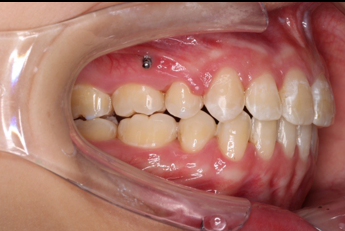

2018.11.14  术后侧面改善明显,露龈笑改善明显,笑弧笑线协调,颏部肌肉紧张度明显改善

2018.11.14  术后磨牙尖牙I类关系,中线齐,覆合,覆盖正常

宏观评价:面部对称,面下三分一比例协调,上下唇凸度正常,上颌牙列内收转矩控制良好,下颌后缩改善,颏唇沟变得更加柔和,术后达到基本直面型。

迷你观评价:上下牙齿中线与面中线对齐,笑弧协调,微笑时牙龈暴露量正常,微笑时横向正常,左右唇基本对称。

微观评价:牙齿整齐,咬合关系良好,上下前牙转矩及突度控制良好,磨牙关系I类,尖窝咬合关系良好,OB,OJ正常。